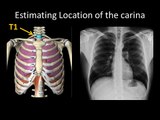

Basic Chest Radiology: ET Tube Position and Complications